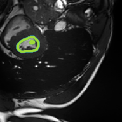

Despite their outstanding accuracy, semi-supervised segmentation methods based on deep neural networks can still yield predictions that are considered anatomically impossible by clinicians, for instance, containing holes or disconnected regions. To solve this problem, we present a Context-aware Virtual Adversarial Training (CaVAT) method for generating anatomically plausible segmentation. Unlike approaches focusing solely on accuracy, our method also considers complex topological constraints like connectivity which cannot be easily modeled in a differentiable loss function. We use adversarial training to generate examples violating the constraints, so the network can learn to avoid making such incorrect predictions on new examples, and employ the Reinforce algorithm to handle non-differentiable segmentation constraints. The proposed method offers a generic and efficient way to add any constraint on top of any segmentation network. Experiments on two clinically-relevant datasets show our method to produce segmentations that are both accurate and anatomically-plausible in terms of region connectivity.